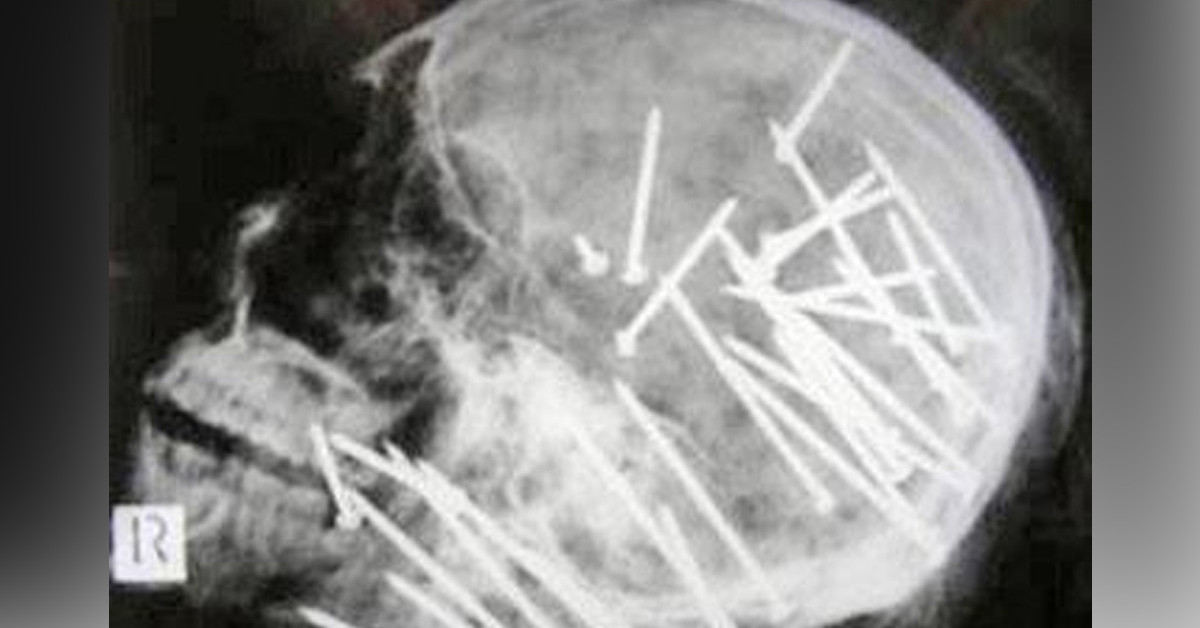

Yorumsuz...